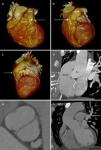

(a–c) Three-dimensional volume rendered cardiac computed tomography images showing the relationship of the coronary artery fistula (arrow) to the right ventricular outflow tract, aorta and main pulmonary artery in anterior (a), anterolateral (b) and lateral (c) planes; (d) curved multiplanar reformatted cardiac computed tomographic image showing the course of the coronary artery fistula anterior to the right ventricular outflow tract; (e) multiplanar reformatted cardiac computed tomographic image showing the presence of a non-calcified bicuspid aortic valve; (f) curved multiplanar reformatted cardiac computed tomographic image showing the presence of a concomitant aortopathy. Ao: aorta; LAD: left anterior descending coronary artery; LV: left ventricle; MPA: main pulmonary artery; RVOT: right ventricular outflow tract.

A 28-year-old man presented with a five-hour history of central chest pain and dyspnea. His 12-lead electrocardiogram demonstrated biphasic T waves in leads V1–V4, and T-wave inversion in lead AVL (Figure 1). He was accordingly treated for acute coronary syndrome and referred for coronary computed tomographic angiography (CTA), which showed unobstructed coronary arteries but also an additional vessel that represented a coronary artery fistula (CAF) (Figure 2a–d). In addition there was a bicuspid aortic valve (Figure 2e), concomitant aortopathy (Figure 2f) and a dilated pulmonary artery. The patient underwent surgical ligation of the CAF and was discharged five days later following an uneventful recovery.